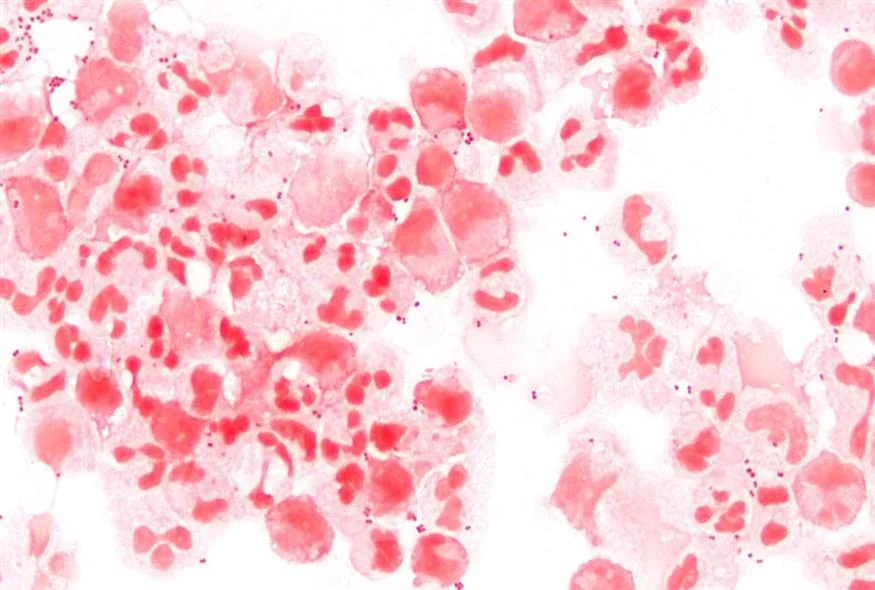

Οι υγειονομικές Αρχές προειδοποιούν τους γιατρούς να είναι σε επιφυλακή για ορισμένους τύπους σπάνιων, σοβαρών μηνιγγιτιδοκοκκικών λοιμώξεων που αυξάνονται.